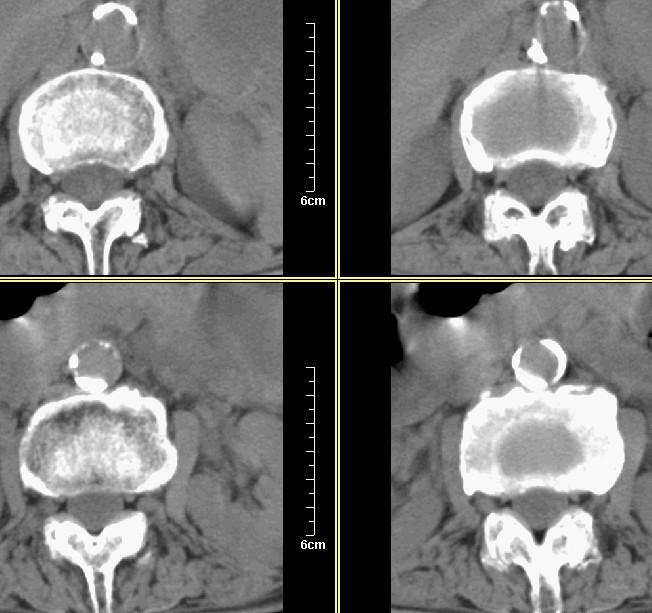

腰1-骶1 间盘及个别椎体扫描

腰3腰4椎体骨质破坏,骨密度低下,骨质疏松,少量骨小梁粗大,紊乱,椎间盘无改变,椎间隙不增宽,椎体无变形,椎旁软组织无肿胀。临床 腰痛明显。考虑:多发淋巴肉芽肿。

支持!几乎累及所有小关节,椎体前缘可见双边影,不排除骨质疏松引起的压缩性骨折。